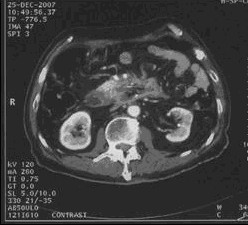

男,68歲,2006年12月14日,CT掃描發(fā)現(xiàn)胰頭占位性病變,6.0×4.7cm2,腹膜后淋巴結(jié)轉(zhuǎn)移,伴肝內(nèi)多發(fā)轉(zhuǎn)移灶。艾恒+希羅達(dá)化療3療程無效(圖1)。2007年4月5日,開始接受今又生治療,胰腺腫瘤內(nèi)注射今又生1×1012VP,共2次,結(jié)合放療45Gy/10f(圖2)。2007年5月12日,IMA64+C,5.3×3.5=18.6cm2,縮小41.0%,瘤囊性化。腹腔灌注今又生5次,1-2×1012VP/次/周,+順鉑60mg,健擇每周1.4g,治療2周。療后1年,腫瘤進(jìn)一步縮小及壞死(圖3)。

治療前